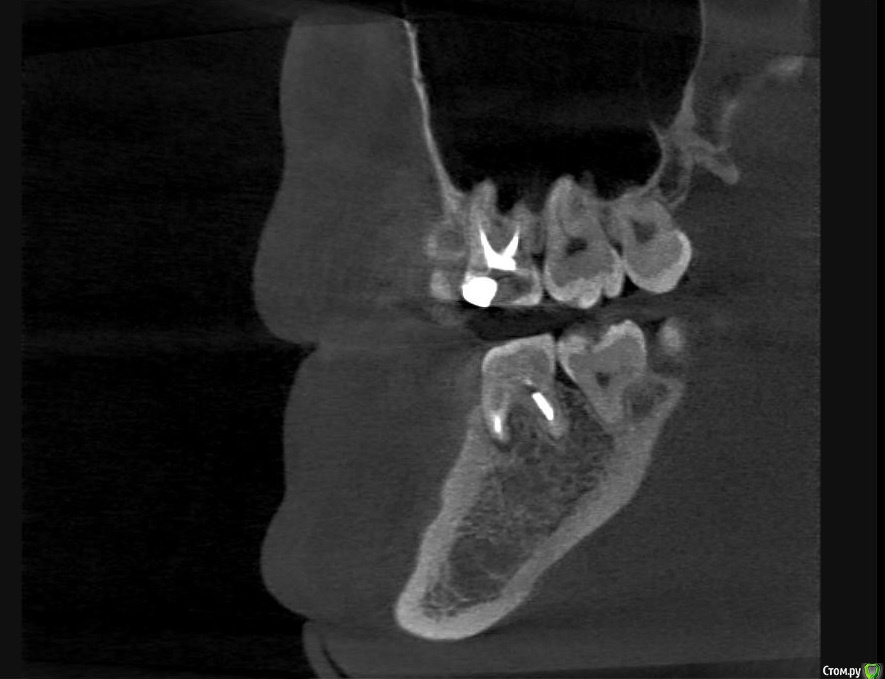

Л Ю С Я Опубликовано 10 января, 2014 Поделиться Опубликовано 10 января, 2014 .Новый кейс-совсем свежий пока без долгосрочного результата.Пациентка попала случайно удаляла зуб 28 и хирург сделал ОПТГ,где стали видны обширные периапикальные процессы в области 37 47.Побывав у меня на консультации и услышав план лечения и стоимость,пациентка решила видимо полечить подешевле.,побывав на консультациях в нескольких клиниках и в итоге даже попала к главному стоматологу нашей области. Все ей сказали что удаление онли. Вернулась,-засада была в том что план я писал исходя из ОТПГ не сделав прицел(виноват),сделав прицел понимаю что все сложнее чем я думал-ну что же тем интереснее.Переписав план лечения и подняв ценник на 40%(пациентке не оставалась выбора),начали лечение.1-посещение-ревизия пломбы.понимаю что кто то до меня с маниакальным упорством пытался запломбировать мезиальный язычный канал каналонаполнителями. Убрал два фрагмента из верхней трети мезиального язычного.2-посещение еще фрагмент из мез язычного плюс немного с дистальными поработал(их оказалось два сплит в верхней трети)3-визит обошел фрагмент в мезиальном щечном и доработал остальные каналы.4-визит -паковка.На предпоследнем снимке видны поры-допаковал(просто на финальном не очень видно)Класс! Ждем рекол через 6 месяцев. Паковка чем? Сквирт? Ссылка на комментарий

Hans85 Опубликовано 14 января, 2015 Автор Поделиться Опубликовано 14 января, 2015 Полагаю на КТ будет не такая уж радужная картинка...Чем завершено лечение? Коронка?Наконец то пациент пришел на коронку.Вот и Кт ,да заживление не 100% ,но все же . 3 Ссылка на комментарий